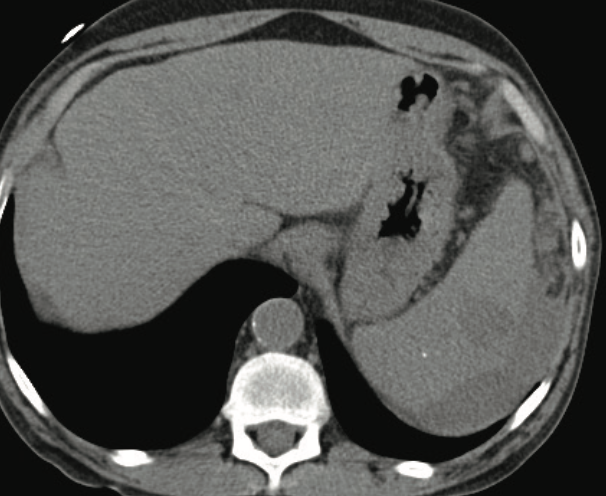

Patients with chronic or critical illness who develop a splenic abscess present an immediate clinical conundrum for the health care team.